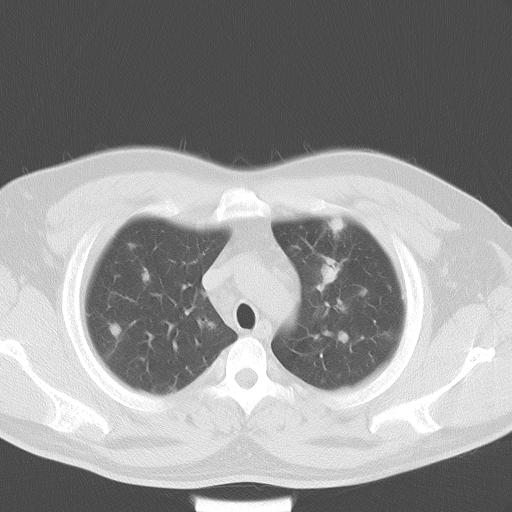

患者男性 35 主因发热咳嗽四天,血象不高,心肺听诊未见异常,无其它病史及传染病接触史。

两肺散在大小不等小结节影,下野较多,纵隔淋巴结增大。考虑:1、慢性血播性肺结核;2、霉菌病?3转移瘤待排。

两肺多发结节,部分病灶边缘不清,且示毛玻璃影。分布特点为沿血管支气管分布。

结合临床考虑;1,炎性肉芽肿性病变;霉菌?过敏性肺炎?2,韦格氏肉芽肿。3,转移瘤。

纵隔内多发肿大淋巴结,两非弥漫性小结节状病灶,分布范围为肺外围为主,首先考虑为肺内和纵隔内转移性病变。(前不久我科室就遇到一女性38岁,肺癌伴肺内弥漫性转移)

双肺散在多发类圆形结节灶,边缘较光滑,纵隔淋巴结肿大,考虑转移瘤

双肺多发结节,部分边缘不清,示磨玻璃样,分布支气管血管走形 考虑:血源性肺脓肿,炎性肉芽肿(韦格肉芽肿)霉菌感染 结节病 转移瘤不除外

肺内多发大小不等结节影,以外周为著,纵隔见多个淋巴结肿大;结果病人,35岁,有发烧咳嗽等病史,首先考虑血源性肺脓肿可能性大,建议积极抗炎治疗后复查,除外转移瘤或韦格氏肉芽肿.

双肺及胸膜下见多发结节影,最大直径约0.4,内密度均匀,中纵隔腔静脉后见小淋巴结影。

经一周抗炎抗病毒治疗复查胸片示病变大部吸收,基本恢复正常,未做气管镜检查,考虑为炎性变或霉菌感染。